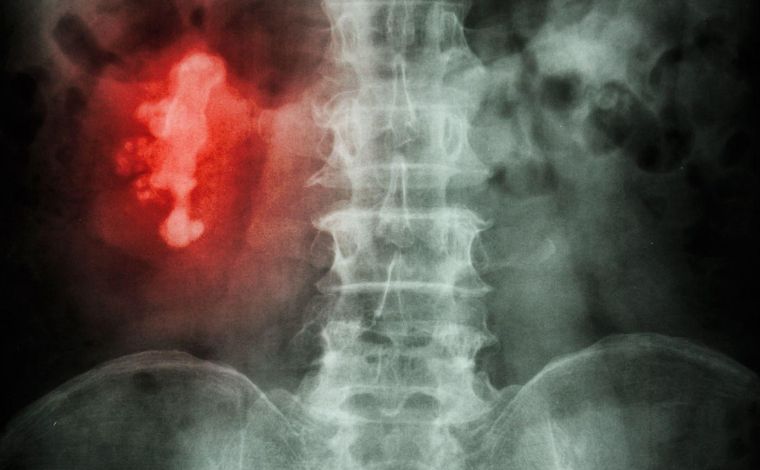

Eles também podem ter formas incomuns: se a pedra se acumular nos canais ramificados (cálices) do rim, ela pode ter o formato de um chifre de um cervo.

Por isso é conhecido como cálculo "chifre de veado".

(Imagem de raio-x detecta uma pedra chifre de veado no rim direito de paciente)